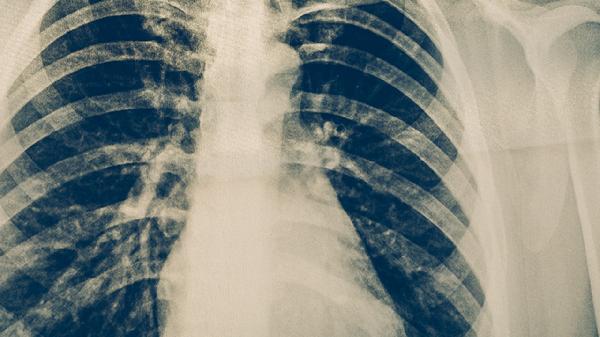

肺結(jié)核是如何傳染的

肺結(jié)核主要通過飛沫傳播,當患者咳嗽、打噴嚏或說話時,含有結(jié)核分枝桿菌的飛沫被他人吸入后可能導致感染。肺結(jié)核的傳播途徑主要有直接接觸傳播、空氣傳播、母嬰垂直傳播、消化道傳播和間接接觸傳播。